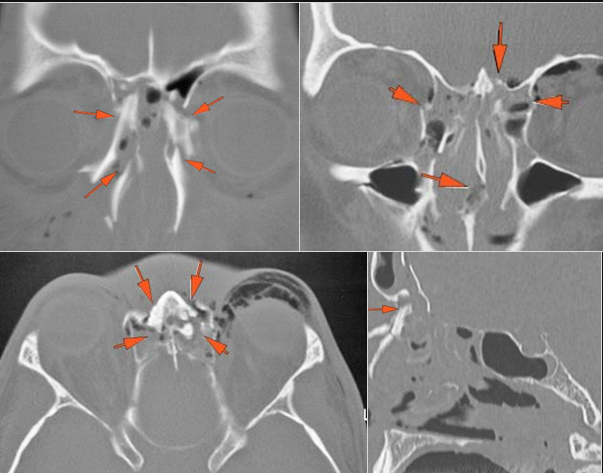

21-year-old male in the emergency room following an altercation with possible orbital or other facial fractures.Exam

There is evidence of herniated intra-orbital fat. |

Yes | NA |

The extraocular muscles are swollen, infiltrated or herniated into a fracture site. |

There is evidence of bony injury along the walls and/or floor of the orbit. |

The mesial naso-orbito-ethmoid complex is fractured. Specifically, there is bony injury of the nasal bones or the frontal process of the maxilla and the medial walls of the orbit are abnormal. |

Orbital floor fracture on the left with significant entrapment of orbital fat and entrapment of the inferior rectus muscle in a likely trapdoor type mechanism and minimally displaced fractures of the medial orbital wall and nasal bones.

Contact ER providers verbally about the finding of likely “trapdoor” herniation of the inferior rectus muscle and strongly suggest the ophthalmology and facial trauma on call be consulted emergently with regard to this finding.

Urgent (Action Necessary in a few hours)